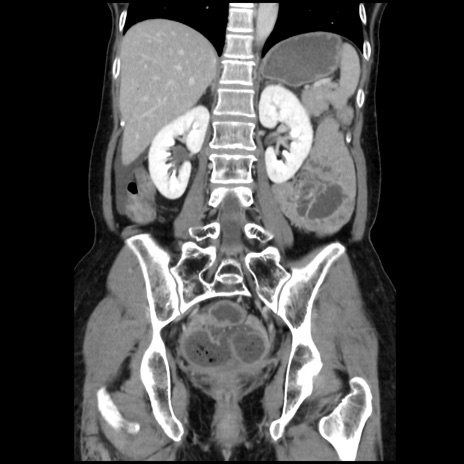

症例32(冠状断像)

【症例】40歳代 女性

【主訴】上腹部痛、嘔気・嘔吐

【現病歴】約9時間前頃から急に上腹部痛、嘔気、嘔吐が出現。改善しないため救急要請。

【既往歴】子宮頚癌(広汎子宮全摘術、放射線療法)、腸閉塞

【身体所見】腹部:平坦、軟、腸雑音亢進、上腹部を中心に腹部全体に圧痛あり。

【データ】WBC 8400、CRP 0.03